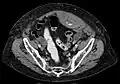

A rectus sheath hematoma is an accumulation of blood in the sheath of the rectus abdominis muscle. It causes abdominal pain with or without a mass.

The hematoma may be caused by either rupture of the epigastric artery or by a muscular tear. Several factors have been identified as predisposing risks for rectus sheath hematoma, including coughing, straining, exercise, hypertension, obesity, previous abdominal surgery, subcutaneous injection, trauma and anticoagulant therapy. With an ageing population and the widespread use of anticoagulant medications, there is evidence that this historically benign condition is becoming more common and more serious.[1] Anticoagulant therapy is used to treat many diseases. However, in the COVID-19 pandemic, anticoagulant therapy was frequently used and therefore the incidence of rectus sheath hematoma increased.[2][3] Given that thrombotic events have been documented in numerous studies, it is advisable to initiate prophylactic and anticoagulant treatment during the early phase of COVID-19 disease.[4]